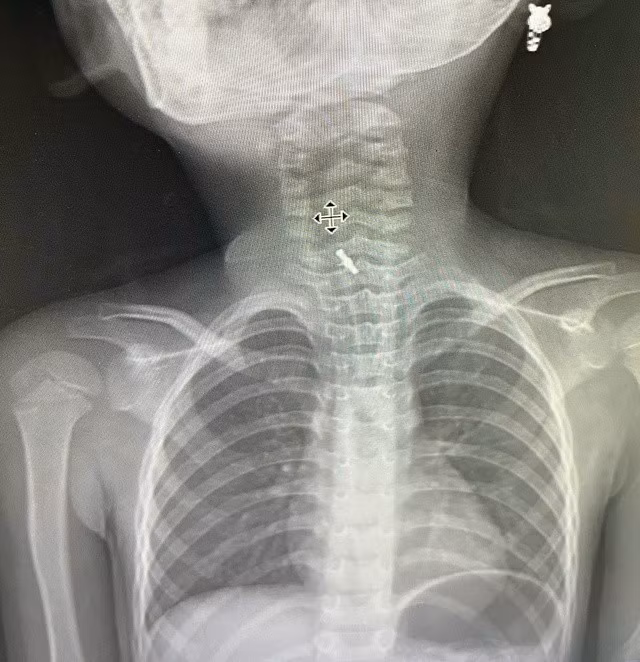

Hình ảnh chụp X-Quang xác định dị vật mắc tại thực quản. Ảnh BV

Tại bệnh viện, sau khi thăm khám và chẩn đoán, các bác sĩ xác định dị vật mắc kẹt trong thực quản. Bệnh nhi được nội soi bằng ống cứng, chiếc kẹp tóc đã được lấy ra an toàn mà không gây tổn thương thực quản.